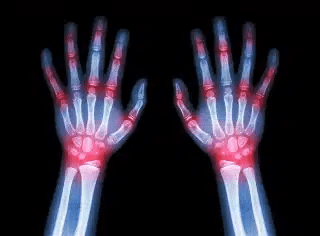

What’s Trending in Infusion Care for Rheumatoid Arthritis This December in Southwest Florida Read More »